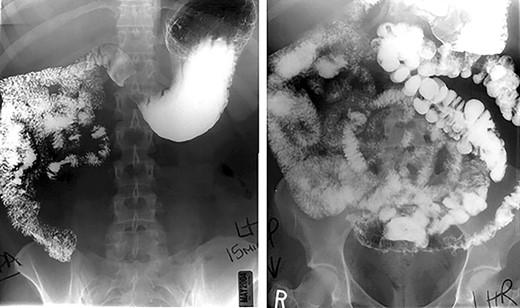

Preoperative work up in two patients (40%) included an upper gastrointestinal series (Fig. 1) revealing midgut non-rotation. The remaining (60%) patients in the series did not endorse gastrointestinal symptoms necessitating an upper gastrointestinal series, IM was identified intraoperatively. In the absence of preoperative diagnosis, malrotation was discovered intraoperatively when the entire greater omentum was found to the left of midline. Confirmation of the diagnosis was based on finding the entire small intestine to the right of midline, the cecum and ascending colon at midline or to the left of midline and the absence of a ligament of Treitz.